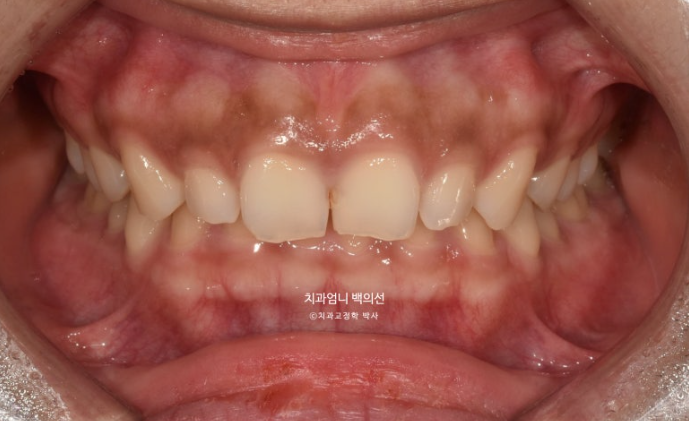

24.03

위 앞니 4개가 전반적으로 짧은 편이고 웃을 때 잇몸이 많이 보이는 거미스마일이 있습니다.

잇몸성형으로 거미스마일을 어느정도는 해결할 수 있지만 앞니가 뒤로 쓰러진 옥니이고 깊게 물리는 과개교합도 있고 앞니 사이도 벌어져 있어서 교정을 권유드렸습니다.

위 앞니가 아래 앞니를 깊게 덮어 아래앞니가 전혀 보이지 않는 정도의 심한 과개교합입니다.

위 앞니는 정상각도보다 뒤로 쓰러진 옥니입니다

앞니 사이사이에 벌어진 틈도 있습니다.